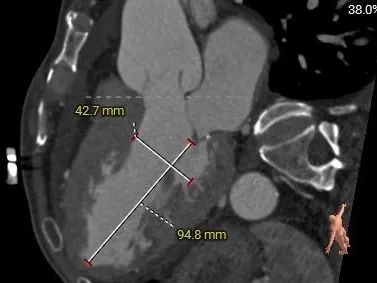

VR图

SOV:

45.8*45*41.3mm

STJ:

41.3mm

AAO:

43.3mm